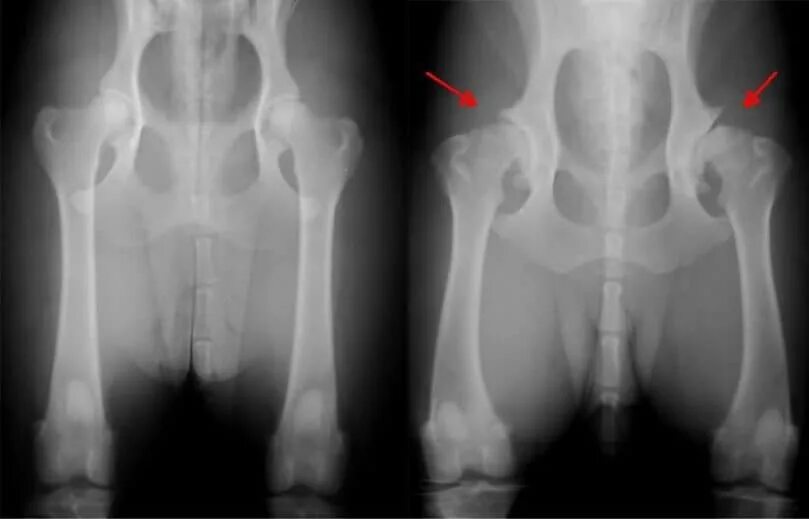

Лечение тазобедренного сустава у собак